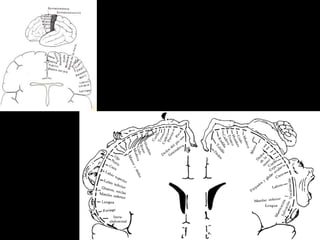

Organos receptores o nosciceptores

Pacini y Meissner para el tacto

Ruffini para el calor

Krause para el frío

Terminaciones nerviosas desnudas para el dolor

Dermatomas